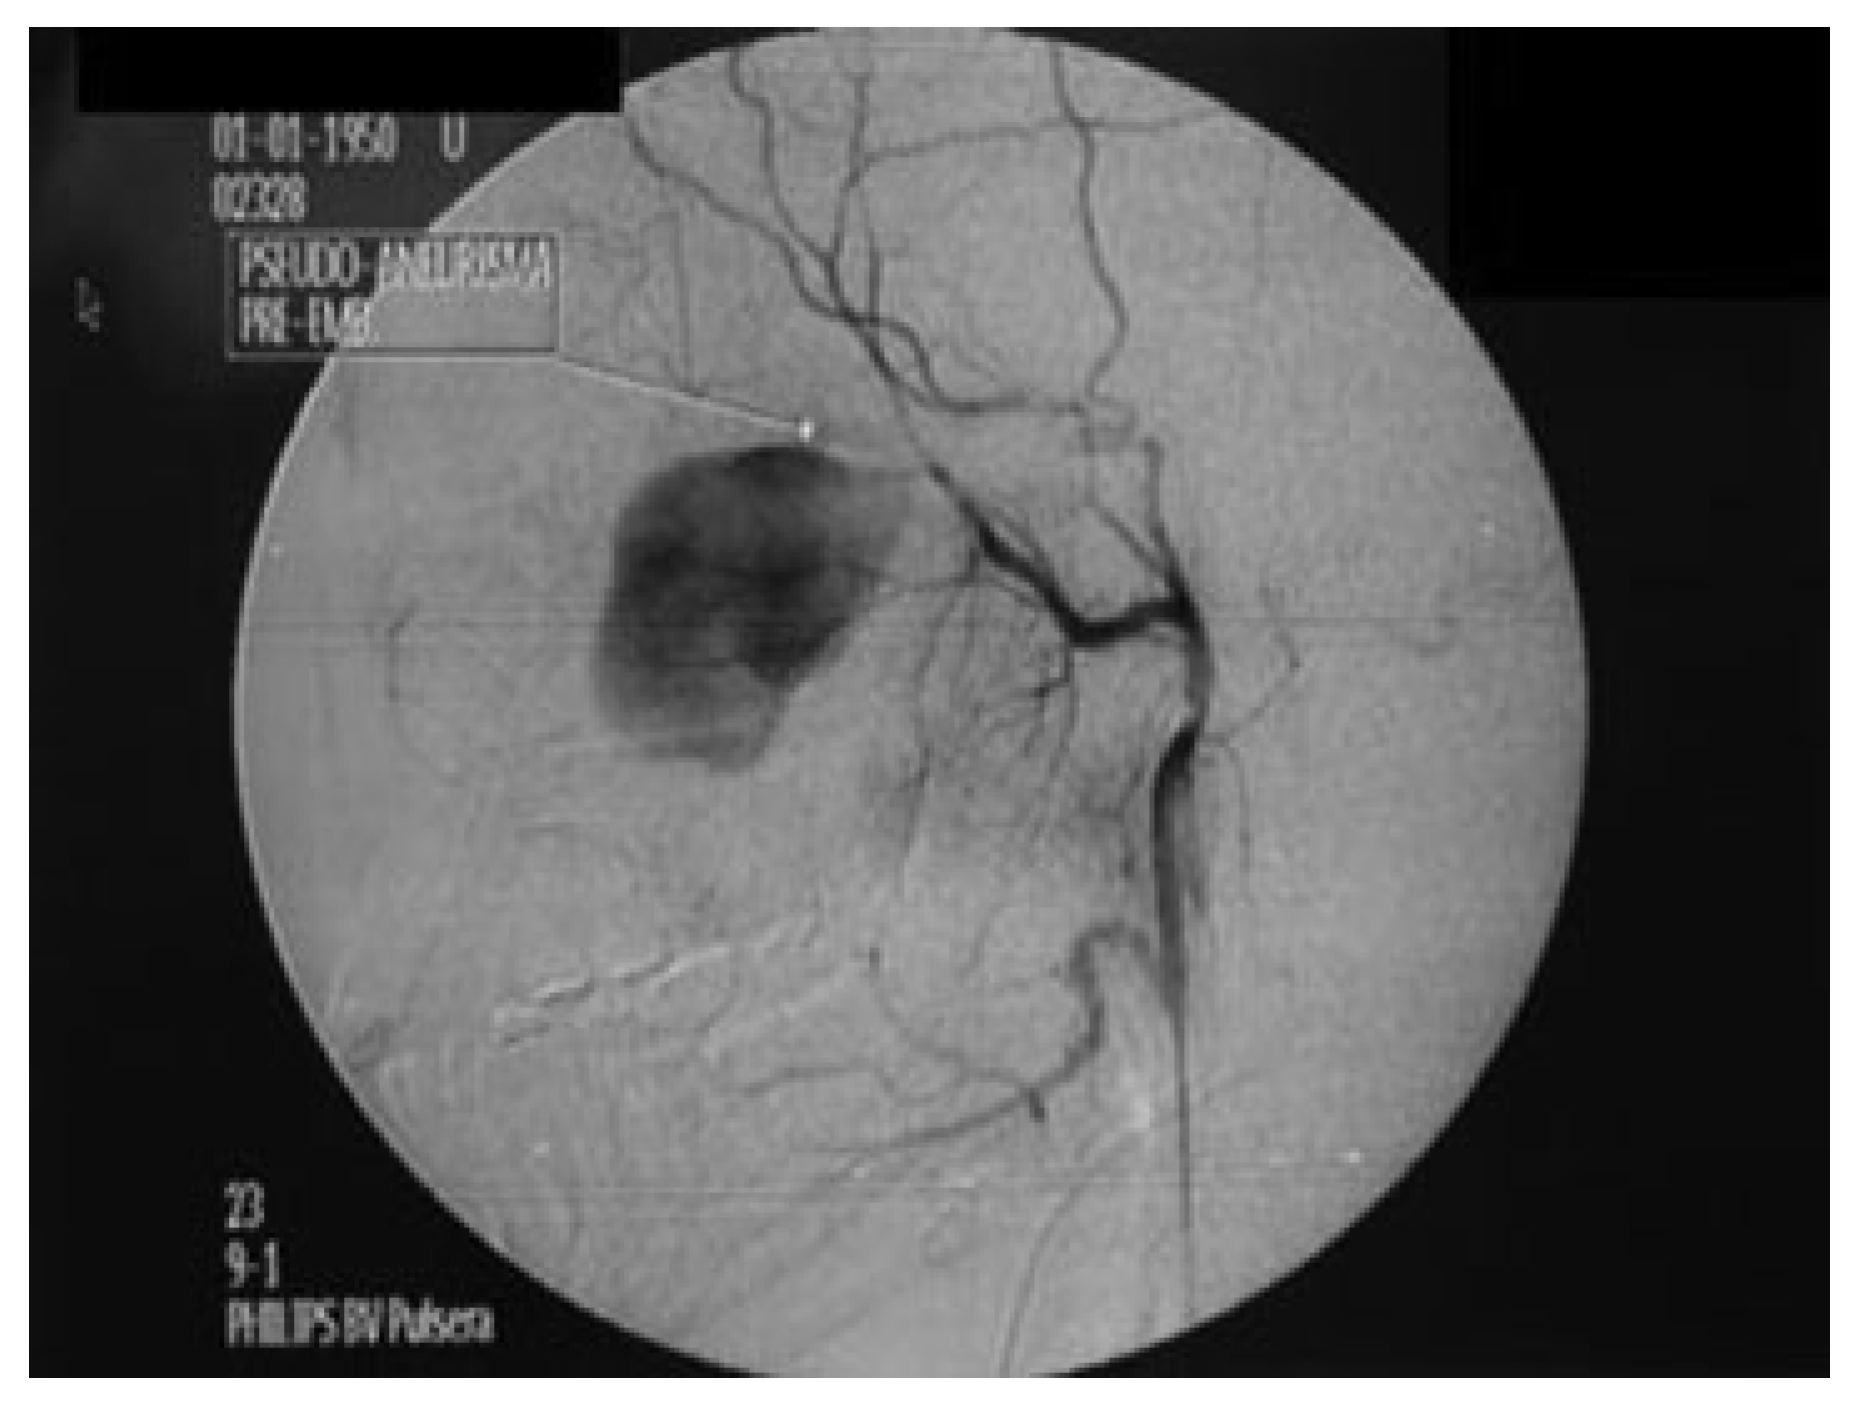

Treatment of Pseudoaneurysm of Internal Maxillary Artery: A Case Report

:Case Report